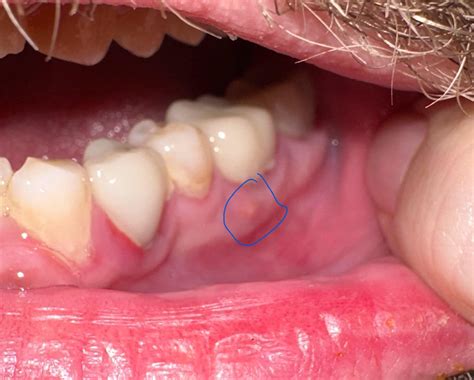

Discovering a pimple on gums can be an alarming experience, often leading to immediate worry about oral health. While it may look like a common skin blemish, a bump on your gum tissue—frequently referred to as a dental abscess or a fistula—is a signal that something deeper is occurring within your oral cavity. Unlike a pimple on your face, which is usually caused by clogged pores, a bump on the gum line is almost always related to bacterial infections, dental trauma, or underlying periodontal issues that require professional attention.

A pimple on gums is rarely just a localized skin issue. In the world of dentistry, this bump is often a drainage point for an infection located at the root of a tooth or deep within the gum pockets. When bacteria accumulate, the body attempts to fight off the infection, creating pus. Since the pus has nowhere else to go, it pushes through the soft gum tissue, resulting in a small, fluid-filled bump.

• Dental Abscess: This is the most common cause. It occurs when a tooth becomes infected due to severe decay or a crack, leading to a pocket of pus at the root.

• Gingival Abscess: Often caused by trapped food debris or sharp objects (like a popcorn hull) piercing the gum line, leading to localized infection.